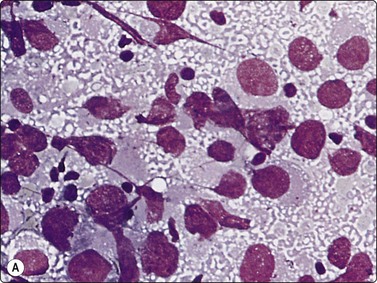

Adenocarcinoma of prostate (Figs 13.5-13.8)4,5,27,34,36,37,39

image image image

Fig. 13.5 Well-differentiated adenocarcinoma

Cohesive sheets of atypical glandular epithelium; mild nuclear enlargement and anisokaryosis; crowding of nuclei; absence of cytoplasmic granules. Note microacinar pattern in B and prominent nucleoli and a mitotic figure in C (A and B, DQ; C, Pap, HP).

In smears of prostatic carcinoma, sheets of benign glandular epithelial cells are commonly seen side-by-side with aggregates of malignant cells (Fig. 13.6), reflecting the diffusely infiltrative growth of the tumor. Benign and malignant cells can be directly compared (very helpful clue) and differences in cytoarchitectural features are easily appreciated. Nuclear enlargement is one of the most important criteria of malignancy. Nucleolar enlargement is better demonstrated in Pap-stained smears.

Absence of visible cell membranes, nuclear crowding and overlapping and dissociation of cells are other important criteria. The presence of coarse intracytoplasmic secretory granules makes malignancy unlikely, but they can occasionally be found in cells from well-differentiated adenocarcinoma. Cytoplasmic vacuolation may be seen in both benign and malignant cells. Nuclear pleomorphism and chromatin abnormalities are obvious in less well-differentiated cancers but may be subtle in well-differentiated carcinomas, rendering a definitive malignant diagnosis difficult (Fig. 13.5). Demonstration of basal epithelial cells by immunocytochemistry may be of help in the distinction between well-differentiated adenocarcinoma and adenosis or basal cell hyperplasia,5 but interpretation is more difficult than in histologic sections. Immunostaining is a useful tool for the diagnosis of prostate cancer at metastatic sites.42 Results may be conflicting in metastases of poorly differentiated carcinomas.

The cytologic presentation is related to the tumor grade. Three grades are recognized.27 Differentiation may vary within the same tumor. Grading is decided by the most malignant pattern seen in available smears, which may not be representative of the whole tumor. Although the correlation between cytological grade and survival has been shown to be very good in a large series of cases,27 most urologists require Gleason grading based on systematic TNCB taken according to a standardized protocol if RP is considered.

Well-differentiated carcinoma may go unnoticed if normal epithelial cells are not present for comparison. The number of cells aspirated tends to be much greater than in samples of BPH, and the amount of background secretion is less. High cellularity on its own may raise a suspicion of malignancy and suggests further investigation by systematic TNCB and serum PSA.

Well-differentiated carcinoma (Fig. 13.5)

Malignant microacini: abundant ill-defined cytoplasm occupying the central zone encircled by a crown of nuclei. Microacini vary noticeably in size and shape. The high frequency of microacini is one of the most important diagnostic criteria,36

Mono- and bilayered large interconnected strands of epithelium,

Few single cells,

Mild anisonucleosis,

Mild hyperchromasia,

Mild or even absent nuclear atypia,

Inconspicuous nucleoli (Pap enhances nucleoli).